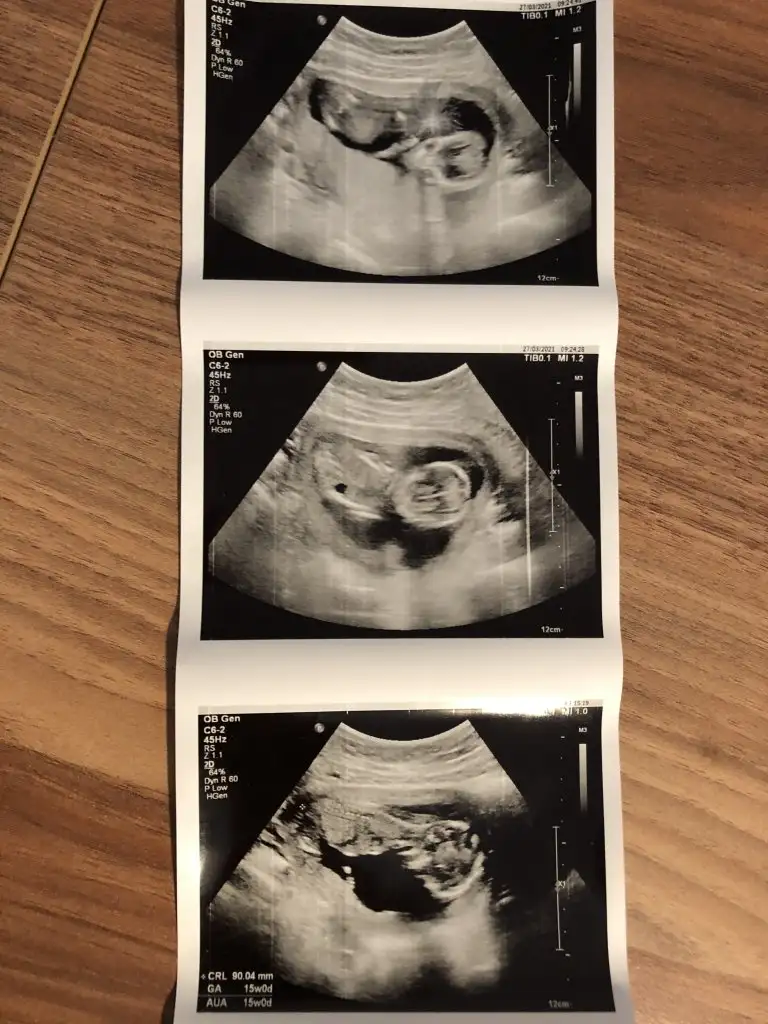

Merhaba Ikra meyra Ikra meyra 11+4te usgmize erkek gibi demiştin. Bugün kontrole gittik bebeğimiz hep poposunu döndü :) bacak arasında da kordon varmış doktor bir türlü emin olup birşey söylemedi. Usg ekliyorum pek nubu görünmüyor gibi ama belki sen görebilirsin :) sonunucu baş aşağı olduğu için onu ters çevirip ekledim. Sana bir fikir veriyor mu acaba 😌

Canım Ikra meyra Ikra meyra bu arada sen kız dedikten sonra iyice inceledim ve 3 çizgi gördüm 🤗 aşağıda işaretledim. Yalnız internette bakarken erkek 3 çizgisinde bizimki gibi birinin ayrık gibi olduğunu gördüm. Sence son kararın ne 😌 kız mı erkek mi? Söz bir daha rahatsız etmeyeceğim seni 🤗

Senin bebek kız görünüyor tipide kız gibi